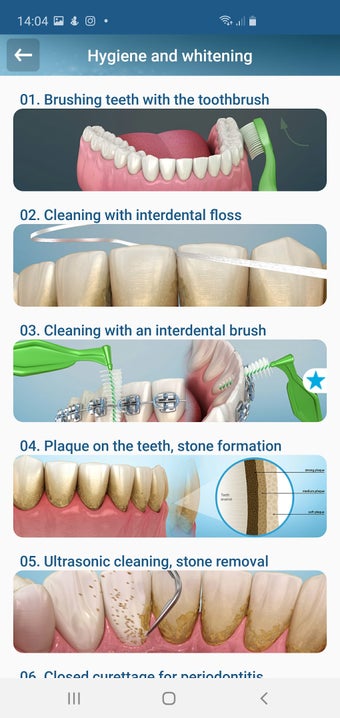

إذا كنت متخصصًا في طب الأسنان أو مريضًا، فقد تساعدك هذه الأداة في تعلم علاجات الأسنان.

تم إنشاء هذا التطبيق بواسطة أليكس ميت للأطباء الأسنان وطلاب طب الأسنان والمرضى. كما يمكن استخدامه أيضًا من قبل المهنيين الطبيين الآخرين.

يستند التطبيق على مبدأ عرض الشرائح. يحتوي كل موضوع على 3-9 صور. يمكن عرض صور أي موضوع في أي وقت.